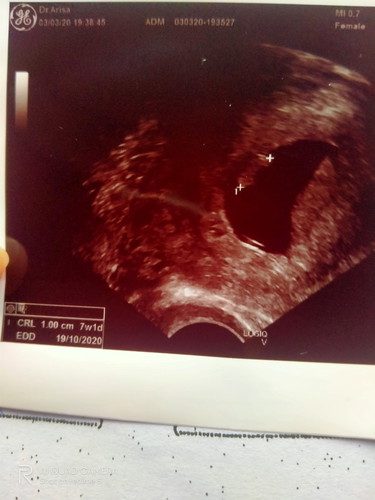

ขนาดถุง 7 w 1d ขนาดเด็กเท่าเม็ดถั่วเขียว คุณหมอว่าไม่สมดุล เด็กยังไมพบหัวใจเต้น คุณแม่บ้านไหนเป็นแบบนี้มั้งคะ พอจะมีลุ้นมั้ย ถ้ารอดเด็กจะแข็งแรงมั้ยคะ